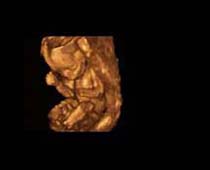

- صور لوجه الجنين في داخل الرحم

- صور جانبية لرأس الجنين

- صور للجنين في المراحل الأولى من الحمل

صور لأجنة ثلاثية الأبعاد بجهاز الموجات فوق صوتية | الدكتور نجيب ليوس